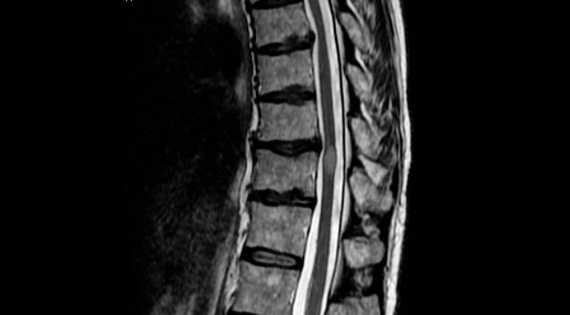

El National Institute of Neurological Disorder and Strokes (NIH) sostiene que la Mielitis Transversa, "es un trastorno neurológico causado por inflamación en ambos lados de un nivel, o segmento de la médula espinal. El término mielitis se refiere a inflamación de la médula espinal; transversa describe la posición de la inflamación -a través del ancho de la médula espinal. Los ataques de inflamación pueden dañar o destruir la mielina, la sustancia grasa aislante que cubre las fibras celulares nerviosas. Este daño causa cicatrices en el sistema nervioso que interrumpen las comunicaciones entre los nervios de la médula espinal y el resto del cuerpo".

Lo que generalmente comienza como el inicio súbito de dolor en la zona lumbar, debilidad muscular, o sensaciones anormales en los dedos de los pies y los pies puede progresar rápidamente a síntomas más graves, que incluyen parálisis, retención urinaria y pérdida del control intestinal.

La enfermedad puede causar daños en el sistema nervioso.